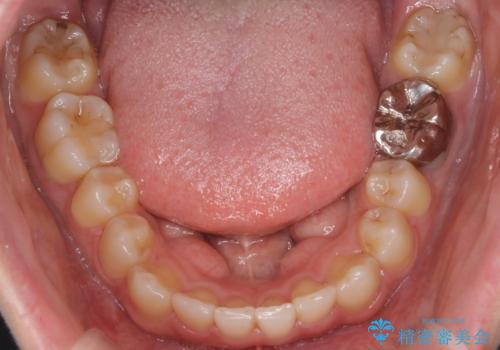

- 八重歯を治したいとのことで来院されました。

右上の犬歯が外側に飛び出して、二番目の歯が内側に入っている状態でした。

上の奥歯を後方に移動させてスペースを確保して、前歯のガタガタを改善する計画としました。